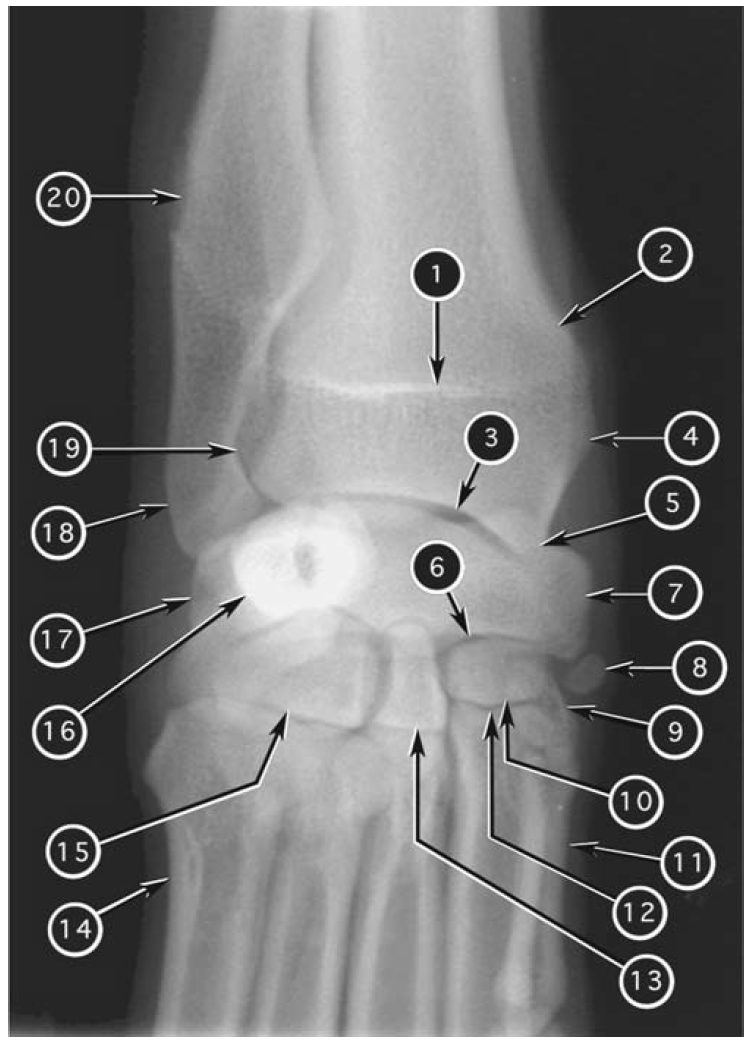

Dorsopalmar radiograph of canine carpus

What number?

- Distal metaphysis of ulna

- Distal epiphysis (styloid process) of ulna

- Ulnar carpal bone

- Distal radioulnar joint

- Distal metaphysis of radius

- Distal physis of radius

- Distal epiphysis of radius

- Styloid process (medial) of radius

- Intermedioradial carpal bone

- Sesamoid bone of abductor pollicis longus

- Antebrachiocarpal joint

- Middle carpal joint

- Carpometacarpal joint

- Accessory carpal bone

- First carpal bone

- Second carpal bone

- Third carpal bone

- Fourth carpal bone

- First metacarpal bone

- Fifth metacarpal bone

A

1. Distal physis of radius

2. Distal metaphysis of radius

3. Antebrachiocarpal joint

4. Distal epiphysis of radius

5. Styloid process (medial) of radius

6. Middle carpal joint

7. Intermedioradial carpal bone

8. Sesamoid bone of abductor pollicis longus

9. First carpal bone

10. Second carpal bone

11. First metacarpal bone

12. Carpometacarpal joint

13. Third carpal bone

14. Fifth metacarpal bone

15. Fourth carpal bone

16. Accessory carpal bone

17. Ulnar carpal bone

18. Distal epiphysis (styloid process) of ulna

19. Distal radioulnar joint

20. Distal metaphysis of ulna